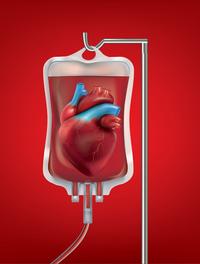

Du sang neuf !

L’Etablissement français du sang fait valoir sa différence.

L’EFS est un acteur vital pour le système de santé français, aussi vital, pourrait-on dire, que le sang l’est pour l’organisme. Acteur public, placé sous la tutelle du Ministère de la santé et de la prévention, il est garant de l’autosuffisance du pays en produits sanguins labiles. Mais pas seulement ! Avec 10 000 professionnels répartis dans toute la métropole et les t